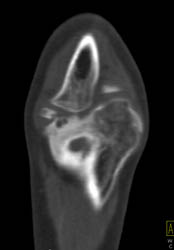

Avascular Necrosis (AVN) With Degenerative Joint Disease (DJD)